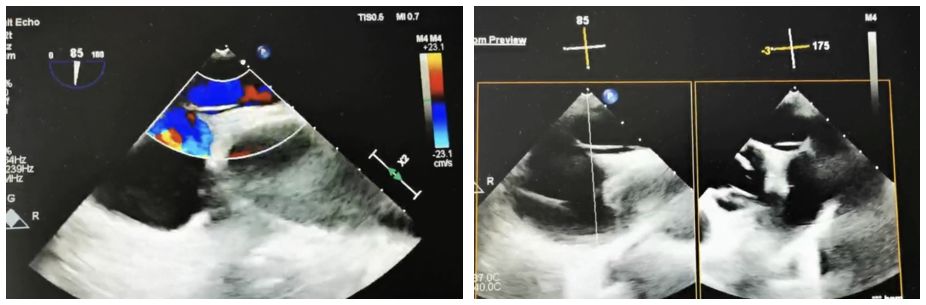

Case Information: A 60-year-old male patient was admitted to the neurology department after experiencing "left-sided limb weakness". The patient underwent a routine transesophageal echocardiogram (TEE), which revealed a patent foramen ovale (PFO) (congenital type, 2.4mm in width, 33mm in length, with moderate shunting). Right heart echocardiography and bubble tests confirmed a grade II shunt.

Stratégie clinique: Nous avons choisi l'occluseur symétrique BDPFO-I 2828 pour assurer une fermeture optimale. Au cours de la phase de libération, l'imagerie DSA a été utilisée pour le positionnement, tandis que le guidage par ultrasons a été principalement utilisé pour assurer un déploiement précis.

Résumé du cas: En raison de la longueur du tunnel, les fils guides de cathéter conventionnels et le support de la gaine de ponction septale n'étaient pas efficaces. Plus précisément, un fil-guide coronaire combiné à une gaine de ponction septale a été utilisé dans ce cas et a traversé avec succès le septum. Lors de l'utilisation d'occluseurs métalliques traditionnels pour les longues fermetures PFO du tunnel, le matériau rigide et la position de taille fixe empêchent souvent le disque gauche de se dilater complètement. Cela peut entraîner le disque à être tiré dans le tunnel, conduisant à un manoeuvres résiduel. En revanche, l'obturateur biodégradable, avec sa forte conformité, a permis à la taille de remplir complètement le tunnel et de réaliser une fermeture efficace.

Cette fermeture réussie valide davantage l'efficacité des occluseurs biodégradables de PFO dans le traitement des cas complexes de PFO.